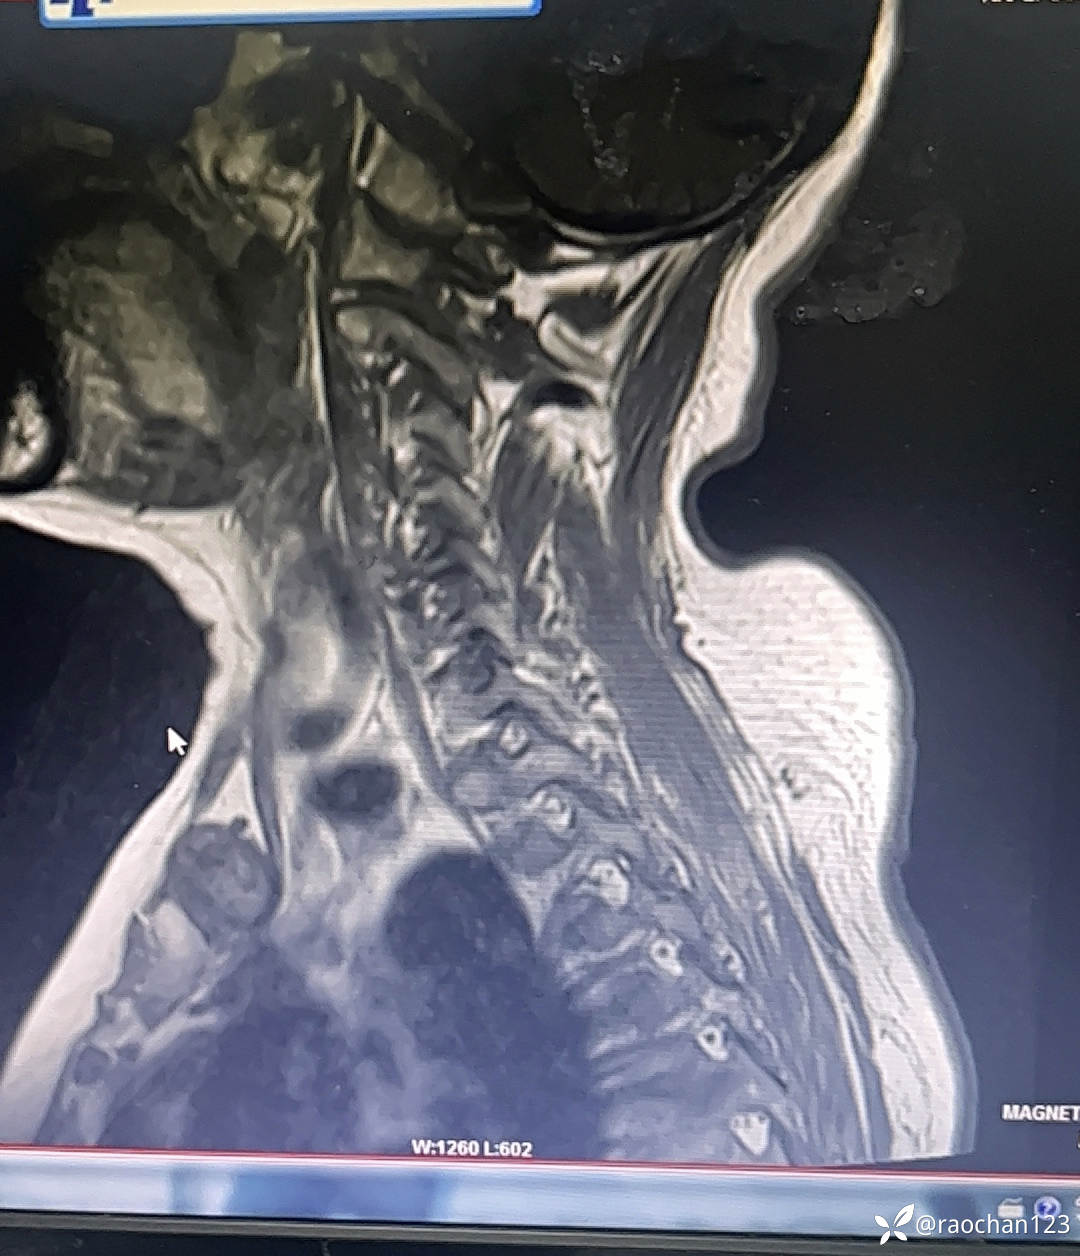

【治疗经过及结果】:给予低流量吸氧,布洛芬混悬液 解热 镇痛,左氧佛沙星抗炎(既往有头孢过敏史)、止痛,热毒宁注射液 清热解毒;艾箱灸、中药塌渍、中药涂擦、火罐、TDP、中药热奄包等中医外治通络祛痛等治疗后,仍有发热,肌酸、肌痛、关节疼痛症状。复查血常规:2024-11-8 13.93# 谷丙转氨酶 45U/L 天门冬氨酸 25U/L 白蛋白 27.0g/L 进一步查乳酸脱氢酶 284U/L 肌酸激酶 26U/L,PCT 0.44ng/ml BNP 811ng/L 免疫五项中IgGA 5.38g/L 血钙 1.94mmol/L 尿微量白蛋白 32.2mg/L 25羟基维生素D 22.68ng/ml 甲胎蛋白、癌胚抗原(-)。颈椎MRI:1.颈椎骨质增生,C4/5、C5/6、C6*7椎间盘轻度突出2、颈后皮下软组织内脂肪堆积,请结合临床。(后颈部皮下软组织内可见异常信号影,T1T2呈高信号,压脂序列呈低信号,颈椎生理曲度变直,椎体后缘连线尚连续,椎体缘骨质光滑,各椎间隙未见狭窄,椎体信号欠均匀,部分椎间盘T2信号减低,C4/5、C5/6、C6/7椎间盘向后轻度突出,硬膜囊轻度受压,椎管无狭窄,黄韧带无肥厚,颈隋未见明显异常)。骨密度:骨质疏松(T值 -4.2)。抗ANA抗体 RF 抗CCP抗体 ENA抗体谱结果待回。患者服用布洛芬混悬液后出现大汗淋漓,血钙偏低,调整为停服布洛芬混悬液、给予醋酸泼尼松10mg 2次/日 口服 解热、抗炎、止痛,金钙尔奇 600mg 2次/日,骨化三醇 0.25ug/日 口服 改善骨质量,暂给予肠内蛋白营养(患者饮食无异常),余治疗同前。